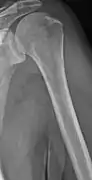

Medical imaging

The diagnostic examination of a person with suspected multiple myeloma typically includes a skeletal survey. This is a series of X-rays of the skull, axial skeleton, and proximal long bones. Myeloma activity sometimes appears as "lytic lesions" (with local disappearance of normal bone due to resorption). And on the skull X-ray as "punched-out lesions" (pepper-pot skull). Lesions may also be sclerotic, which is seen as radiodense.[47] Overall, the radiodensity of myeloma is between −30 and 120 Hounsfield units (HU).[48] Magnetic resonance imaging is more sensitive than simple X-rays in the detection of lytic lesions, and may supersede a skeletal survey, especially when vertebral disease is suspected. Occasionally, a CT scan is performed to measure the size of soft-tissue plasmacytomas. Bone scans are typically not of any additional value in the workup of people with myeloma (no new bone formation; lytic lesions not well visualized on bone scan).